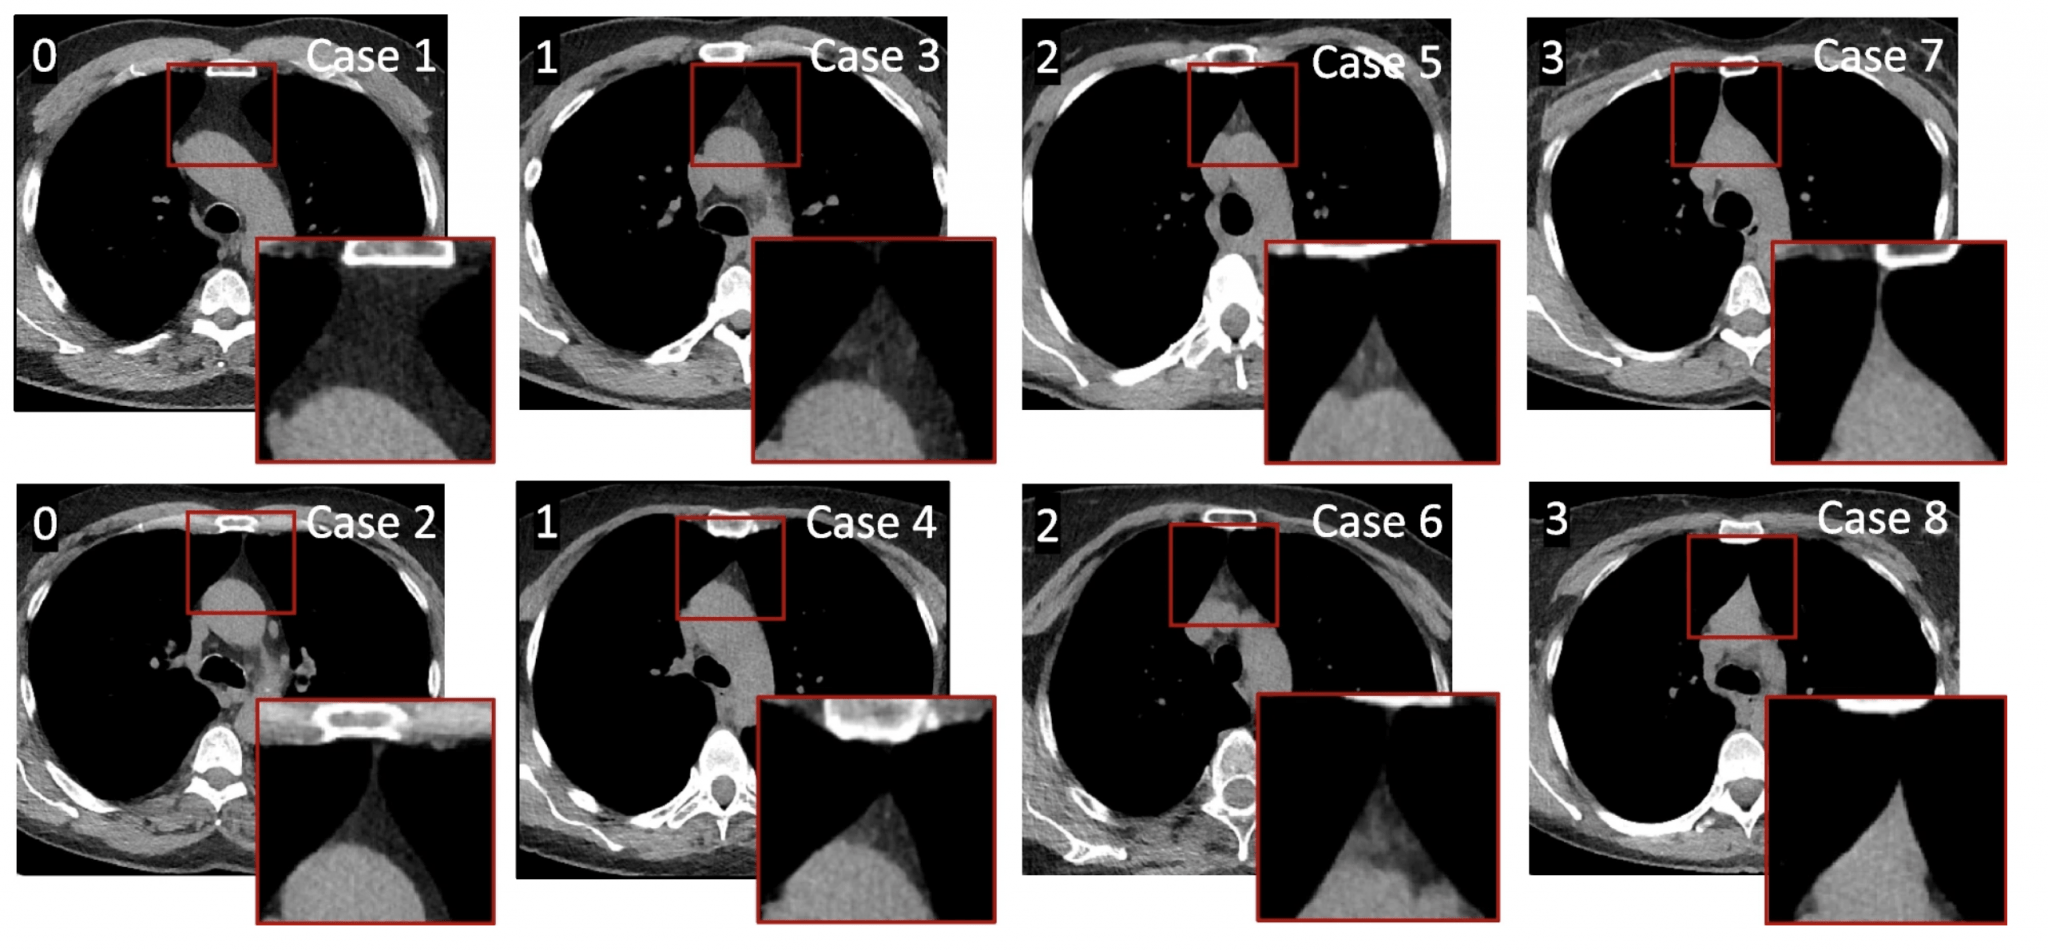

Definition of radiographic thymus variants by CT Imaging. Definition of Thymus Injections Web the main treatments for thymus cancer are: This process is thought to. Radiation therapy for thymus cancer. Web thymomas account for the vast majority of thymic neoplasms and are often associated with autoimmune or neurological. Web the goal of infusio’s thymus therapy is to return the cellular immune system to a balanced state with a series of thymus peptides. Thymus Injections.